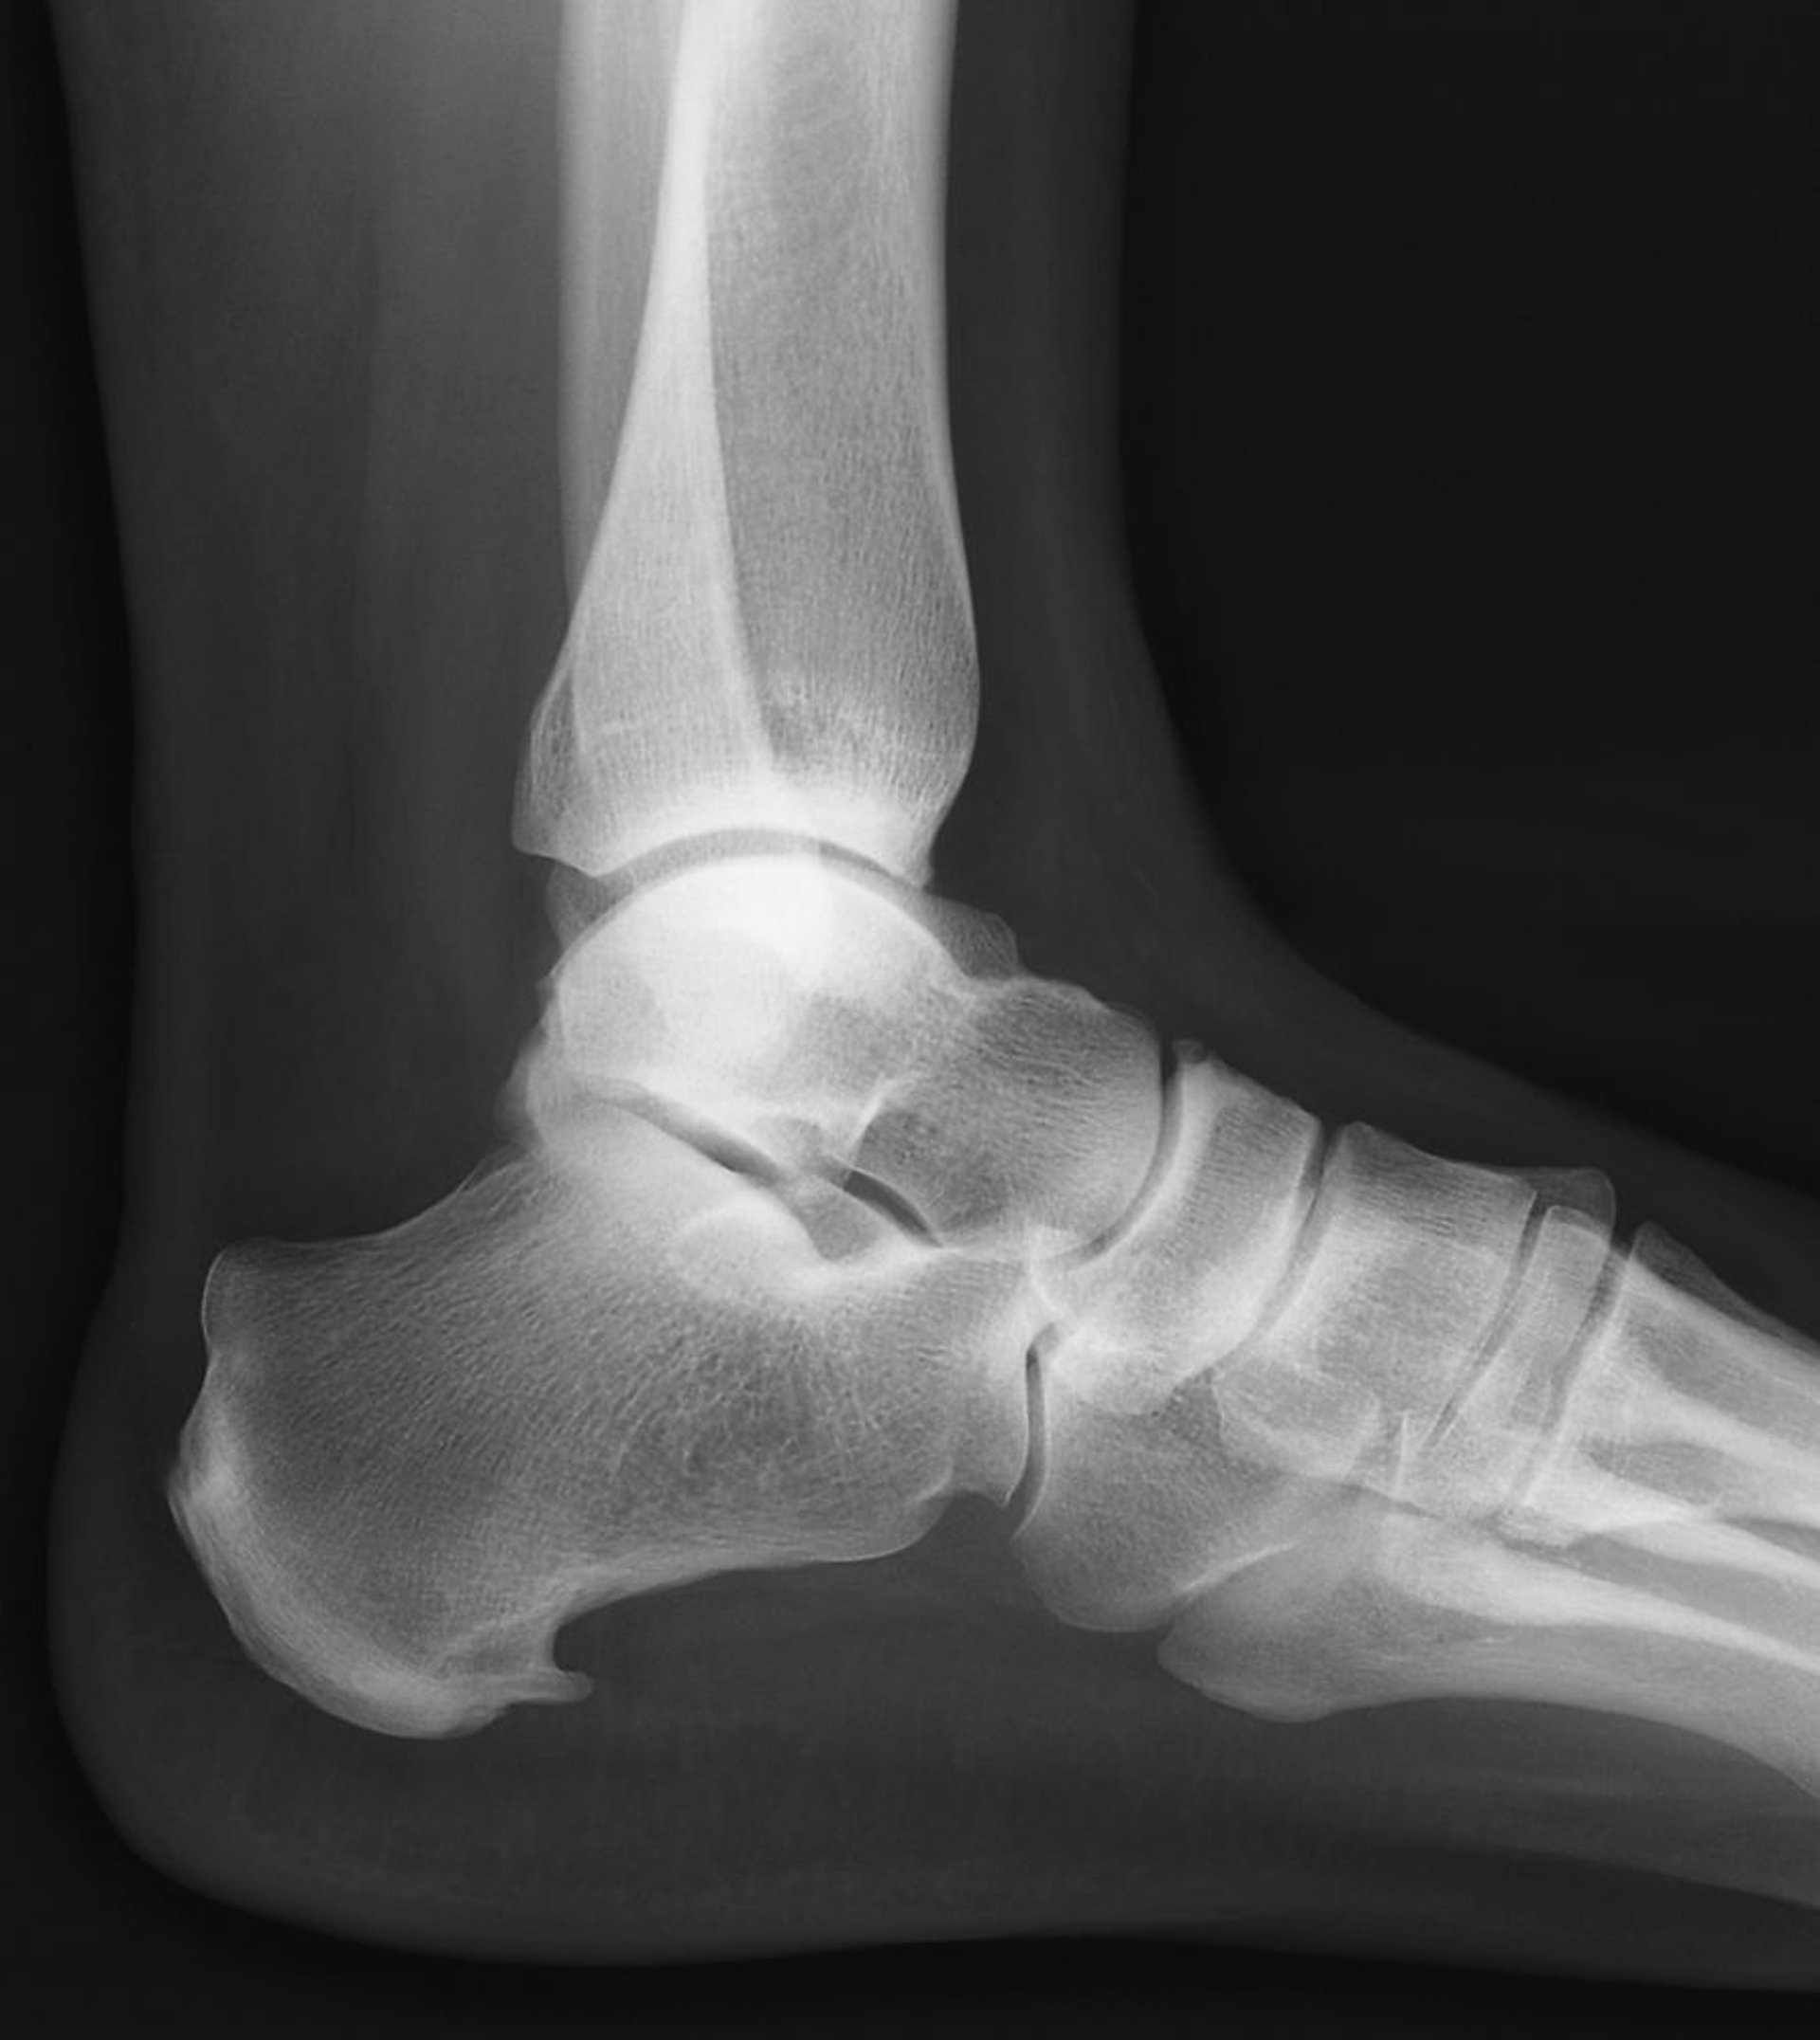

El espolón calcáneo es la exostosis ósea que se extiende hacia adelante en la parte inferior del calcáneo.